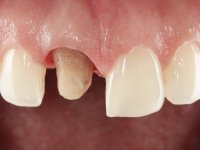

The patient was asked to remove the infiltrated crown and make a new crown with a ceramic-coated Zr infrastructure. As aesthetically, the crown was very well achieved, the patient and her dentist showed doubts about the need or not to intervene immediately. After clarifying my position on the infiltrated interfaces, we decided to jointly intervene. In these situations, the sooner you intervene the better

A pre-print was performed to make a crown in dual-cured resin. After a cross-section with a turbine, the infiltrated crown was removed with a microluxador. The dental stump was re-prepared to better define the shape and location of the cervical margin. It was necessary to place composite resin on the buccal surface of the provisional crown to improve its esthetics. The impression was made using a double-mix technique with two-viscosity, quick-setting silicones. In the laboratory, a crown with a ceramic-coated Zr infrastructure was made. After placing it in the mouth, we verified that the crown showed a greater translucency than the symmetrical one, not fulfilling our aesthetic goals. The ceramist had the opportunity to observe the situation in the clinic, collecting records for later rectification. The new crown was placed in the mouth and approved by the patient. The final cementation was done with resin-reinforced glass ionomer cement.